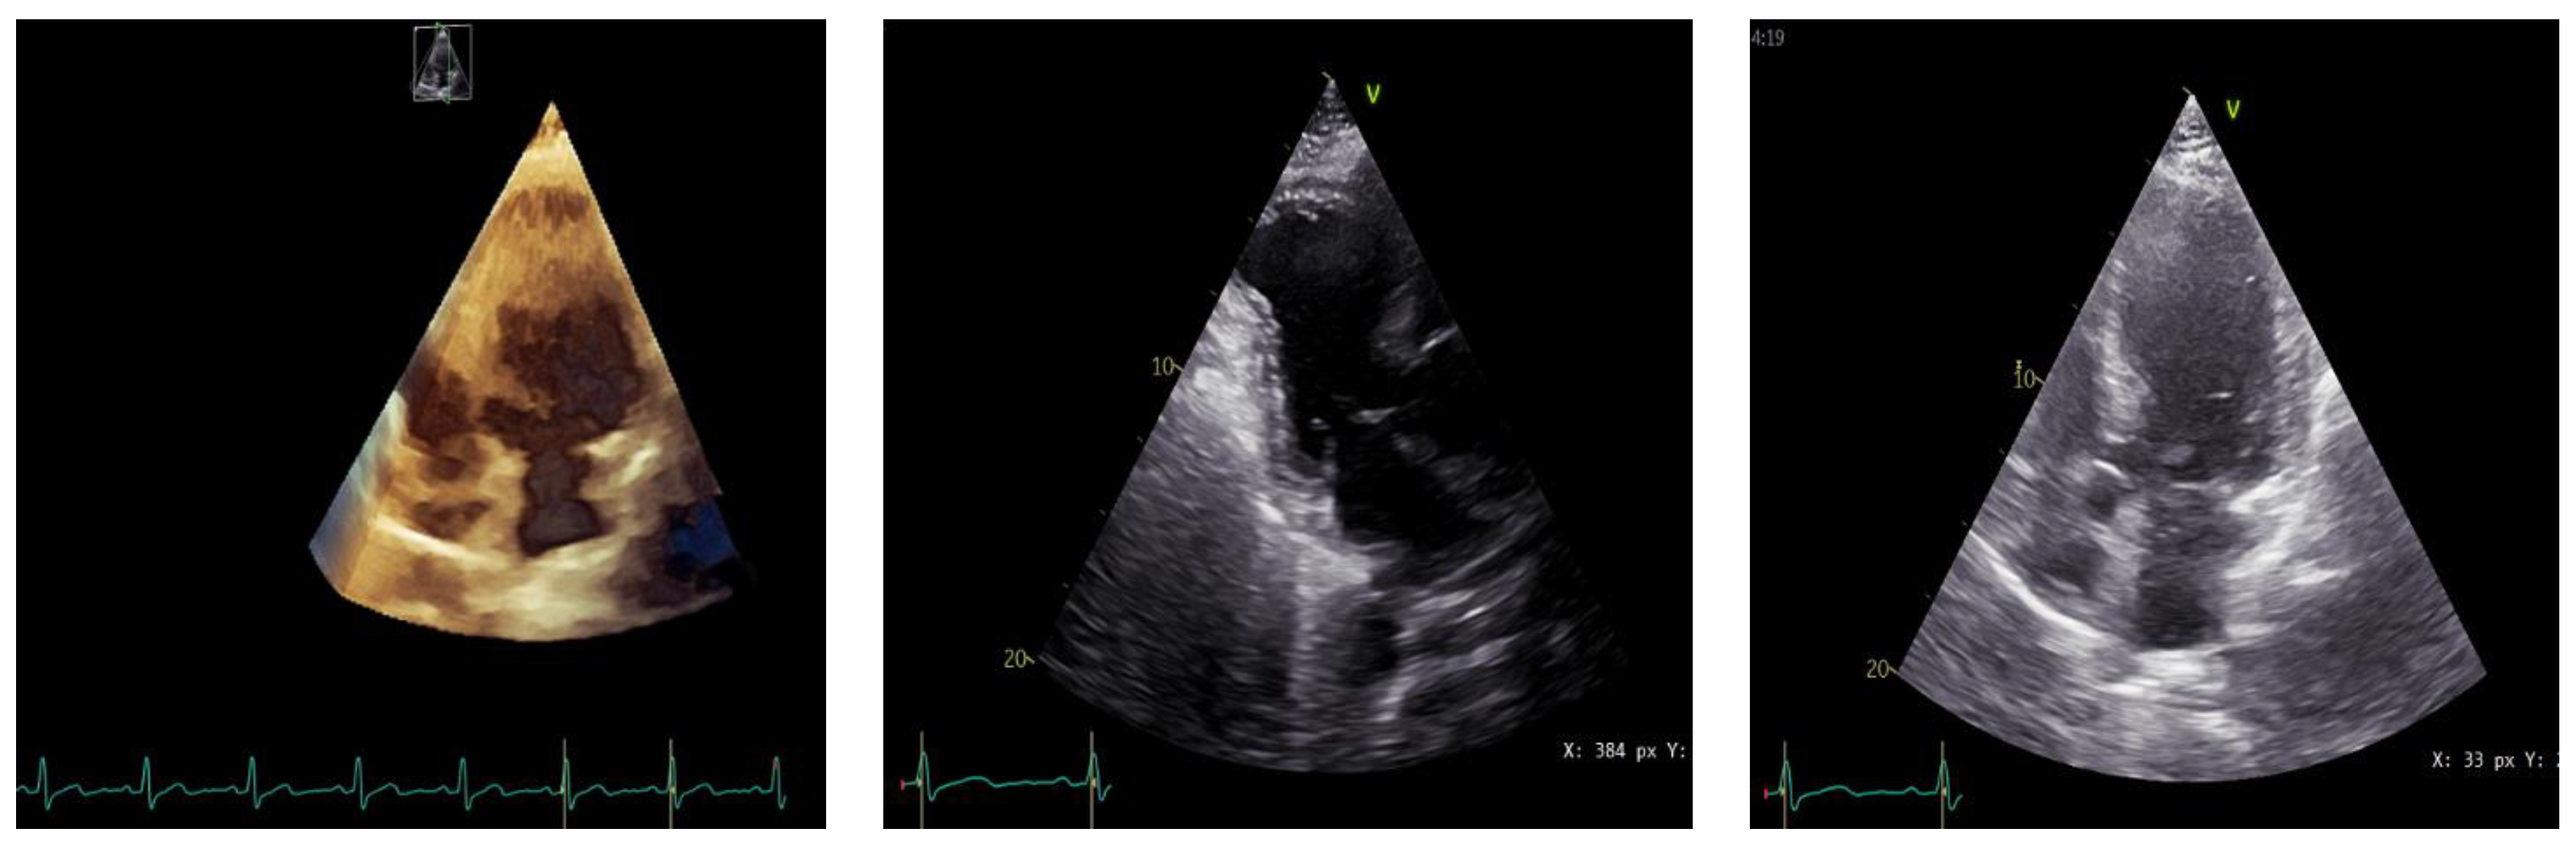

T and Small Protrusion (TAP) Technique in Bifurcations: Coronary Artery Disease in Acute Myocardial Infarction Patients after COVID-19 Pneumonia

2. Case Presentation